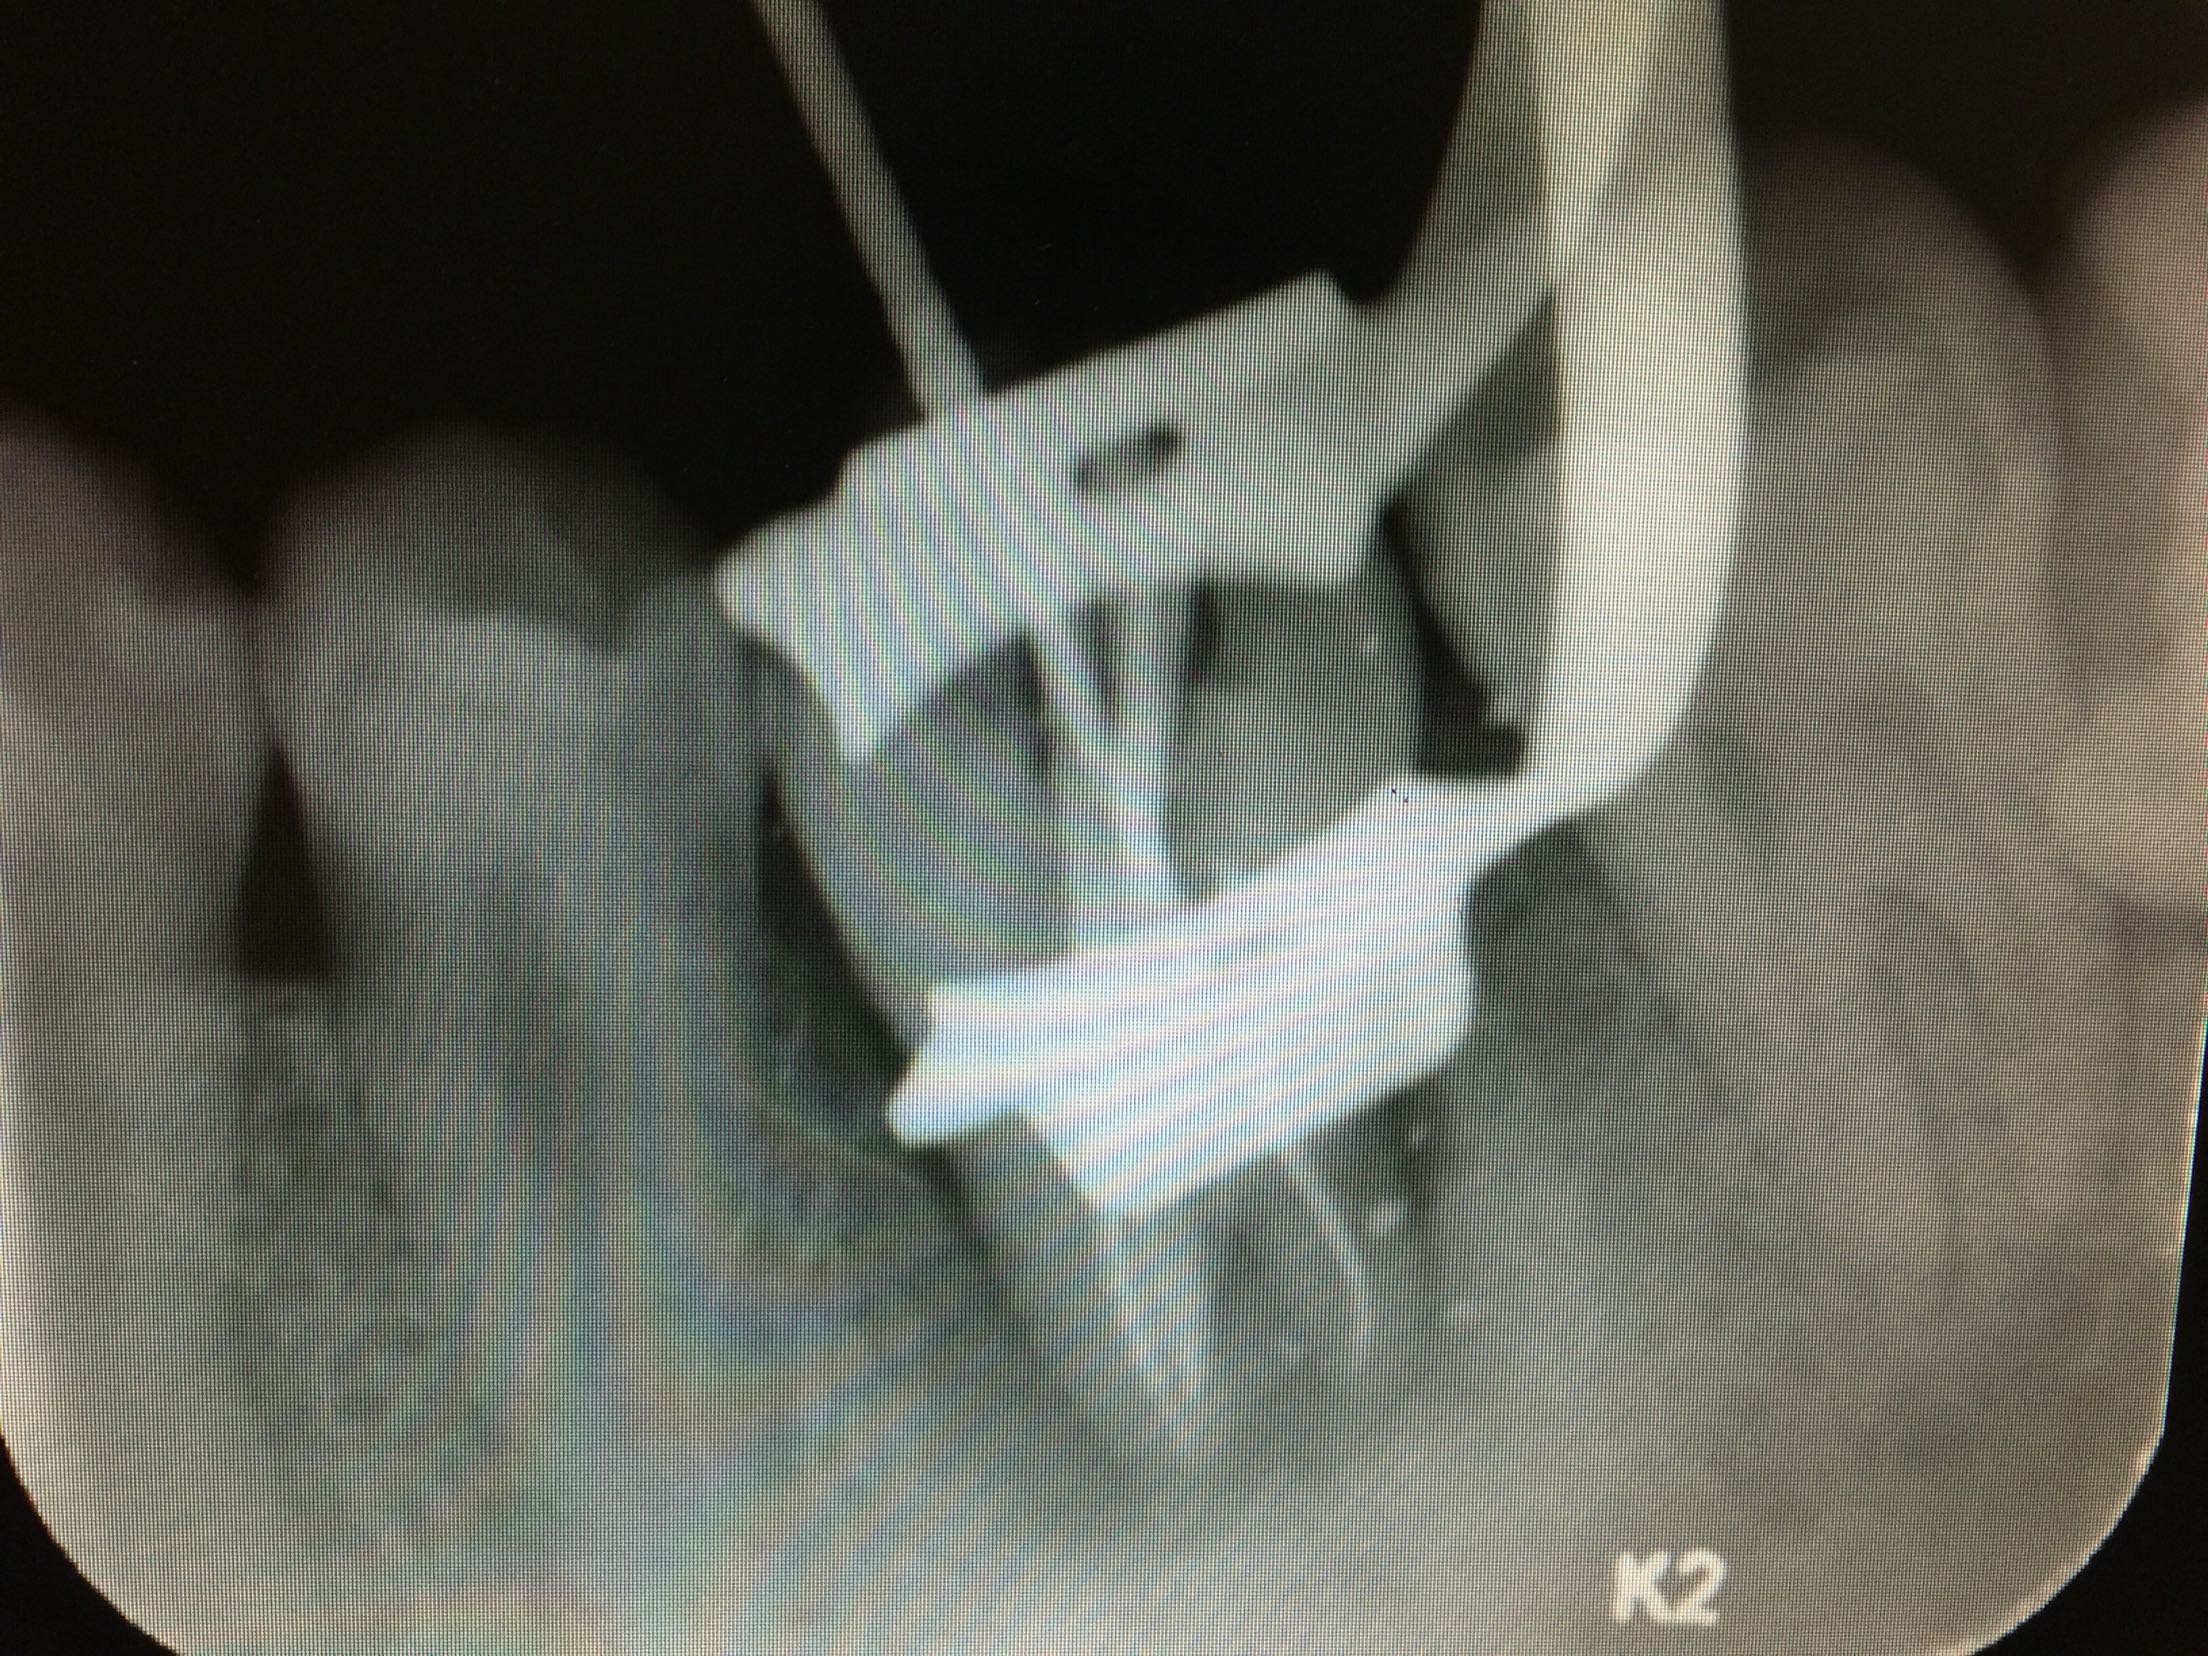

碧蓝麻局部浸润,36(48)牙开髓揭髓顶,探查根管3根,牙髓摘除术,k挫初步预备,根管测长仪测量根管长度,各根管内导入根管润滑剂EDTA,Protaper镊钛器械预备根管,冲洗,超声荡洗,水溶性氢氧化钙充填根管,暂封,约复诊。 复诊:一周后,诊间无不适,36牙暂封完好,冷-,探-,叩-,不松。 试主尖

根充